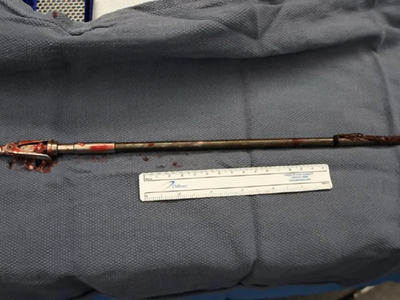

Self inflicted speargun injury to head

Ouch...poor guy...